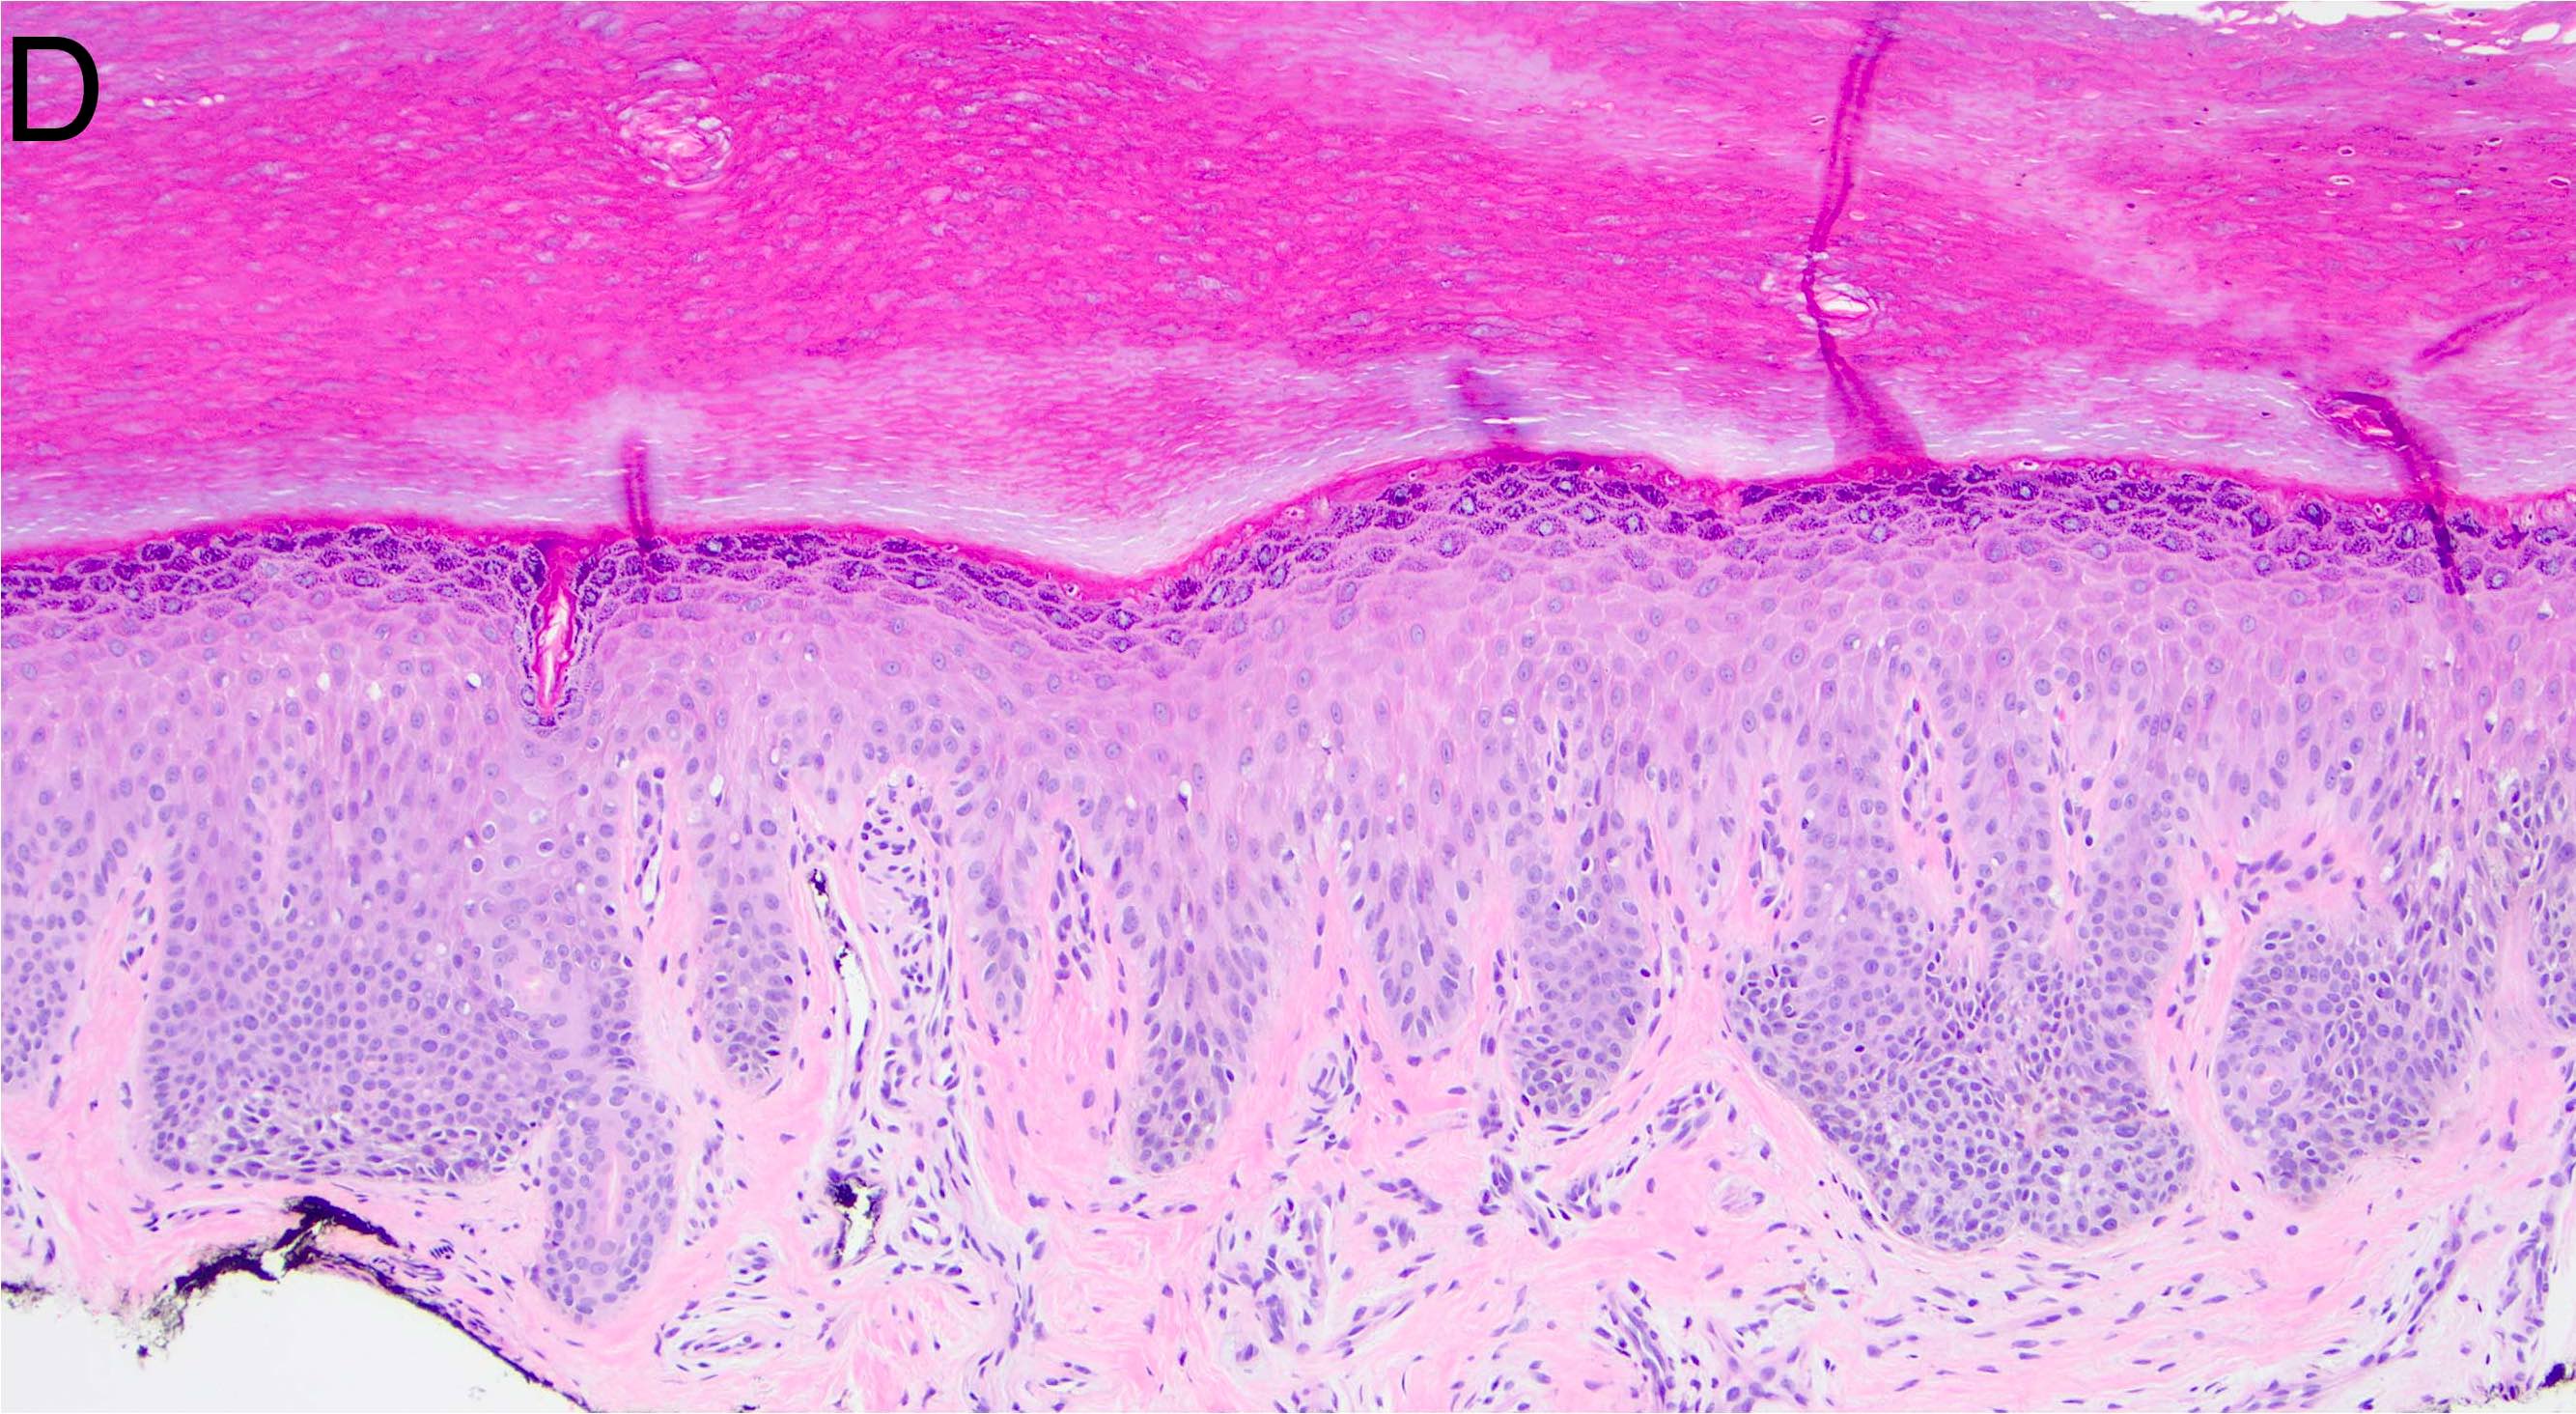

Microscopic (histologic) images

- Melanocytic nevi of the genitals (Am J Surg Pathol 2008;32:51):

- May contain large dyshesive irregular nests in close proximity to one another

- May contain a prominent lentiginous component

- Deeper nests may evoke a stromal fibrotic host response

- Lesion should maintain symmetry, circumscription and maturation

- Pagetoid growth can be seen but typically does not extend into granular layer

- Junctional component may extend into adnexal structures

- Significant cytologic atypia can occur